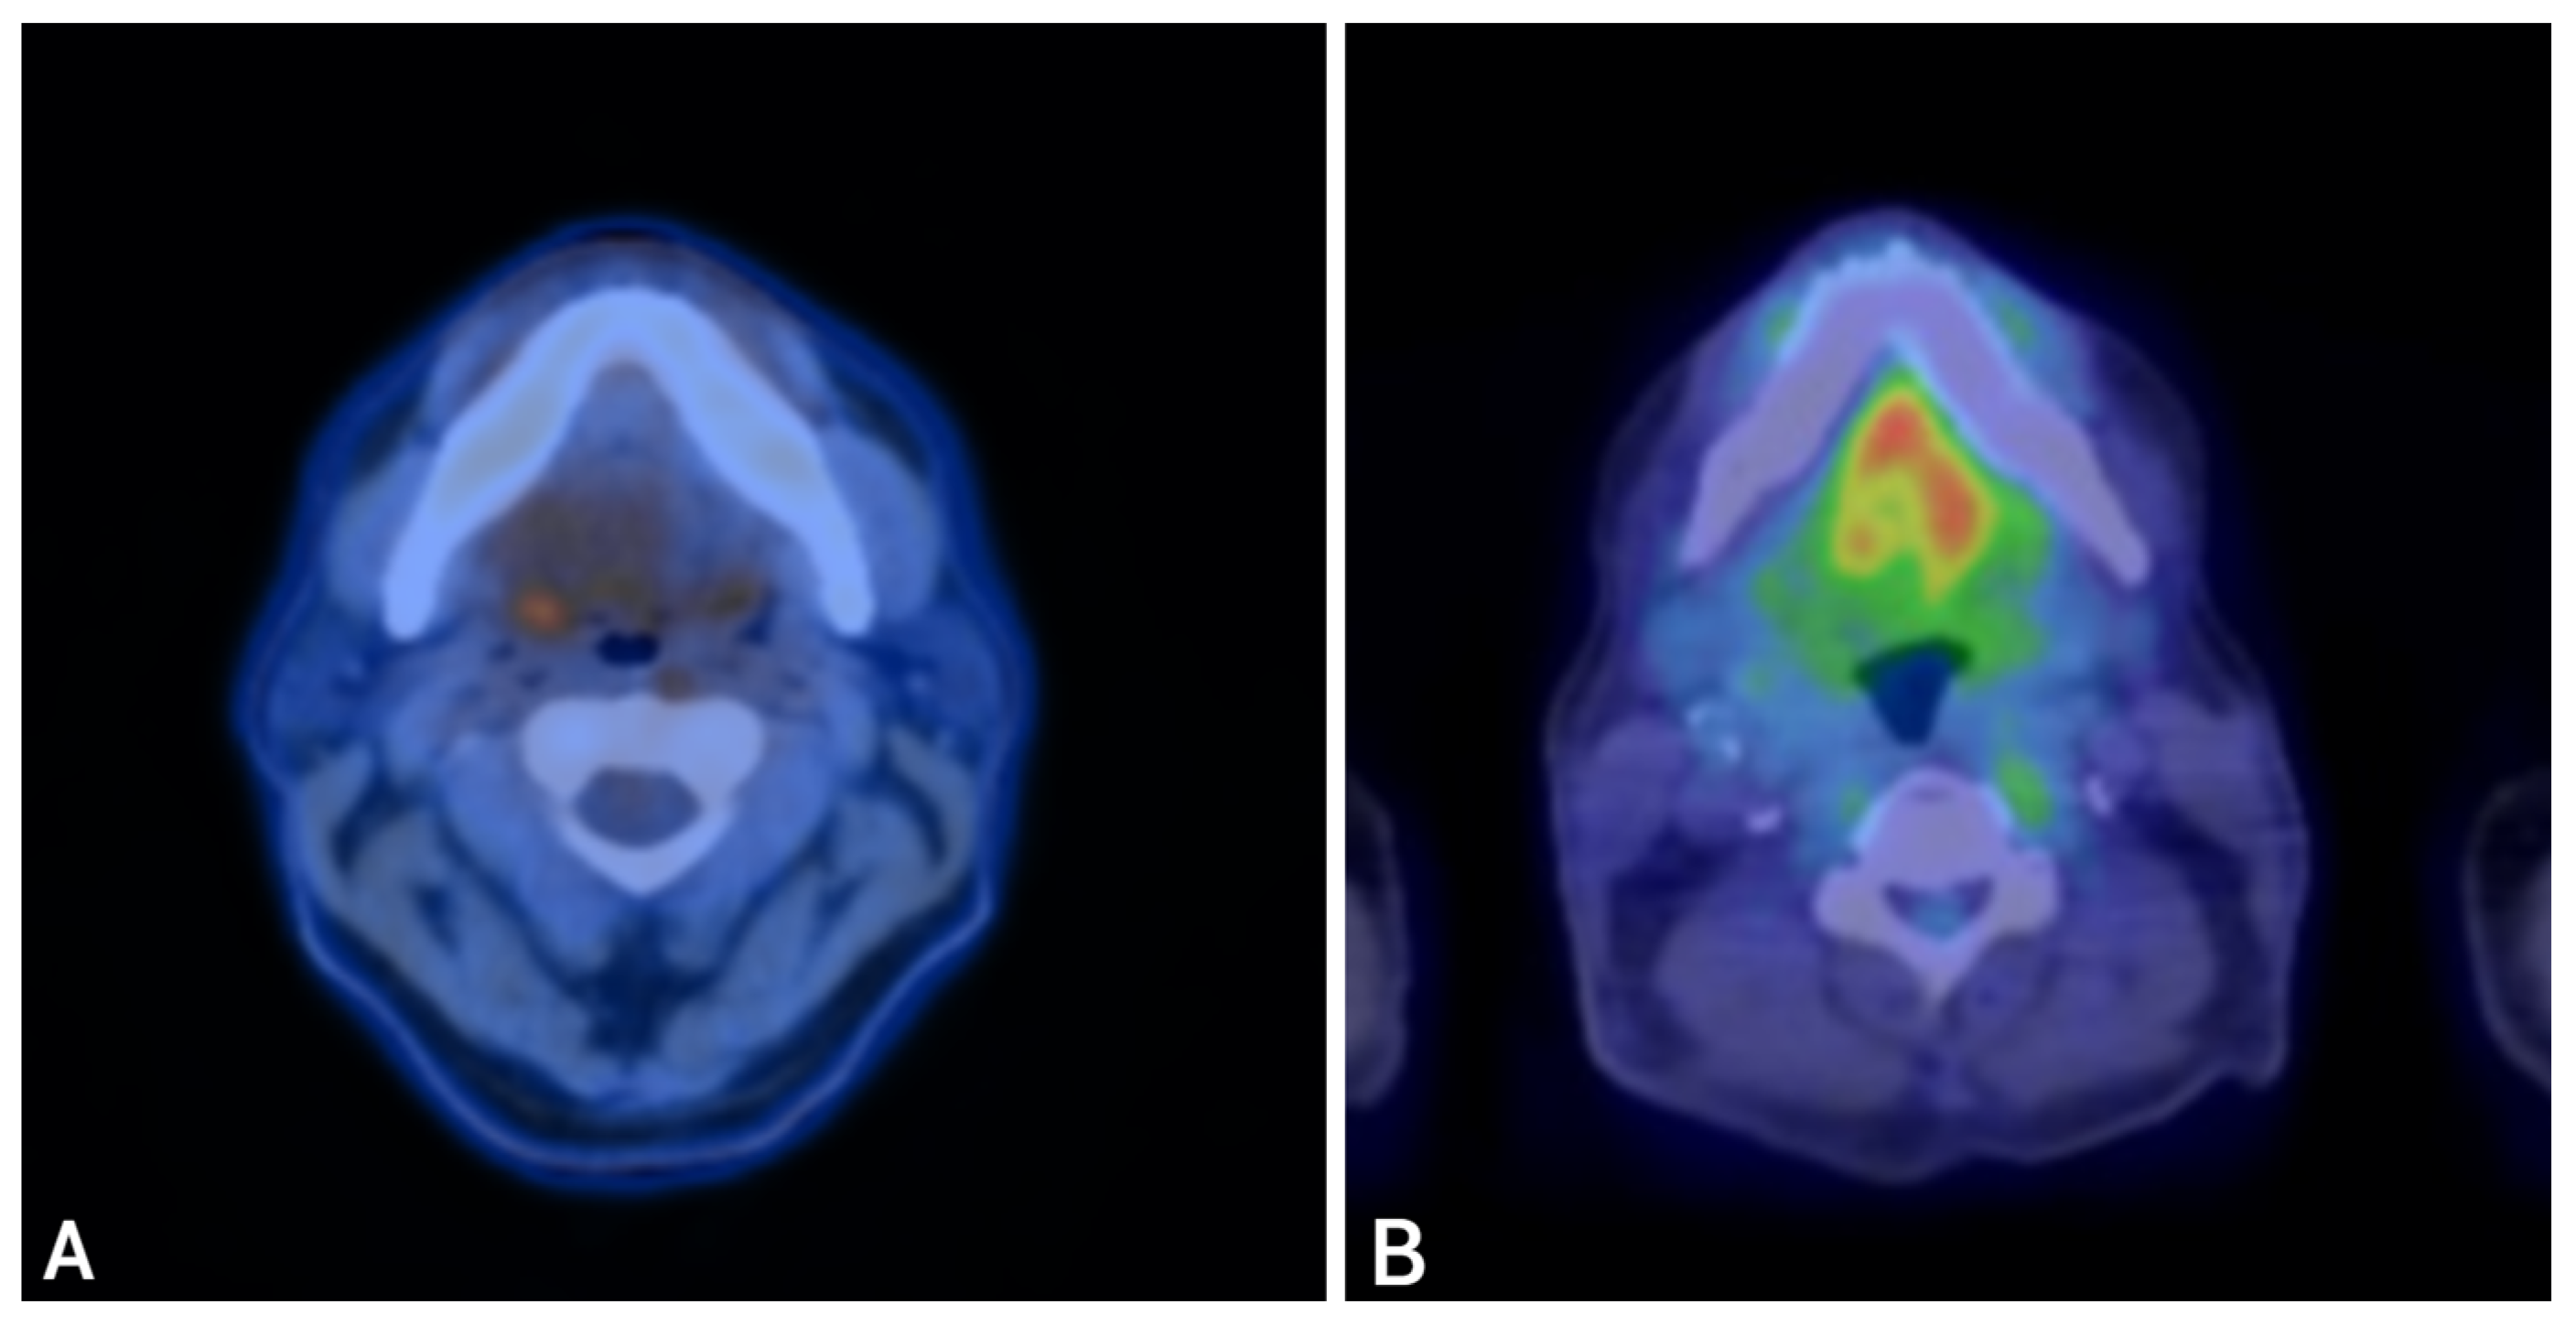

PET-CT on April 5, 2023, confirmed FDG-avid disease in the presacral region, bilateral lungs, left inguinal and right iliac chain lymph nodes, and right penile crus (Figure 2A–D). PSMA-PET revealed a concordant uptake in the same regions. The patient was subsequently evaluated in the CUP clinic at Mayo Clinic. The overall findings, including the patient’s history, persistent NKX3.1 expression, and diffuse PSMA uptake, favored a dedifferentiated prostate carcinoma with divergent enteric morphology. Given CDX2 positivity and prior progression on docetaxel, a histology-driven approach was adopted using FOLFOX (leucovorin, 5-fluorouracil [5-FU], and oxaliplatin). After six cycles, FDG PET-CT demonstrated a complete metabolic response (Figure 2E–H), sustained on the 3-month restaging scan. He was subsequently maintained on 5-FU and leucovorin.

Figure 2.

PET-CT imaging before and after fluoropyrimidine-based therapy in Case 1. Legend: Representative PET-CT images demonstrate FDG-avid disease at multiple sites before therapy and the response after fluoropyrimidine-based treatment. Pre-treatment (Panels (A–D)): FDG-avid disease involving bilateral lungs (A), presacral pelvic mass (B), pelvic lymph nodes (C), and right penile crus (D). Post-treatment (Panels (E–H)): Restaging PET-CT images show complete metabolic response at all previously involved sites, with resolution of FDG uptake (E–H).